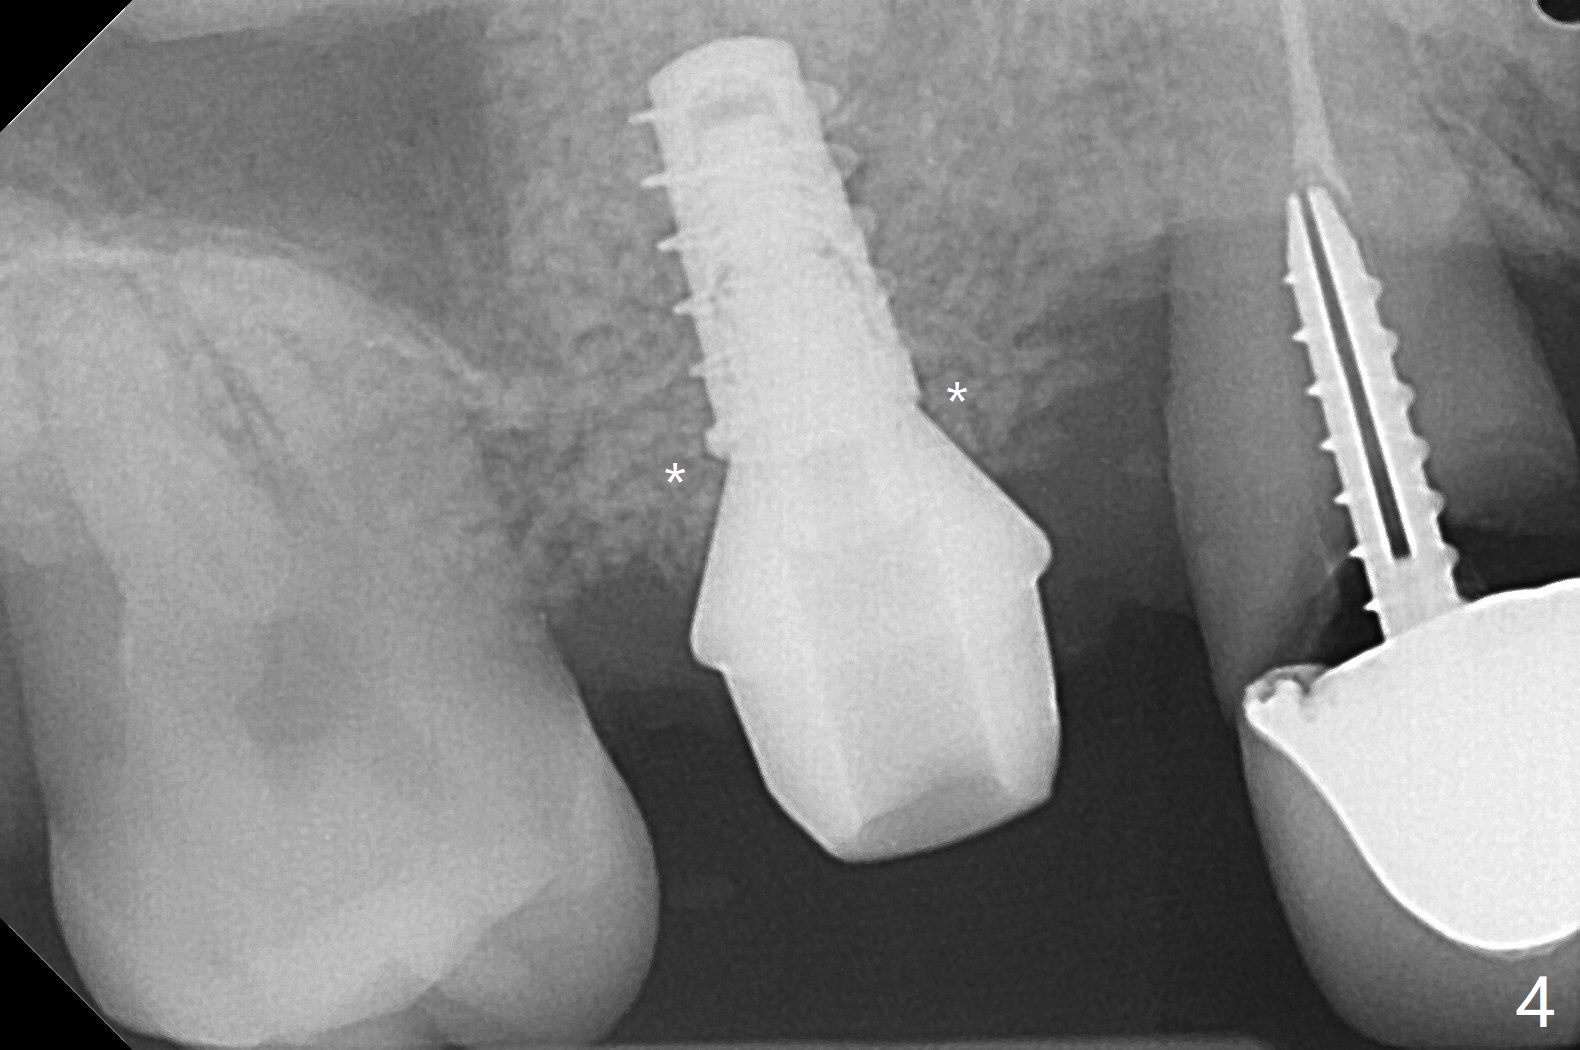

49岁女(个子小)牙齿问题多,同意先做右上5,6种植,6骨质高度1-2毫米,一个月前因动脉出血外提升失败。今天她回来做内提升,同意如果条件合适,同期徒手植牙(将来做一个磨牙牙冠),事先服用阿奇霉素。使用粘性骨粉和报废植体做内提(图一:*),最后植入4x7毫米植体(35Ncm),近中颊侧平牙槽嵴(图二:*),其余骨上 (图三: *),不敢植入太深,怕掉入上颌窦。第二个预防掉入上颌窦措施是利用大号基台(图三),然后在基台周围放置骨粉(图四:*,五),缝合,牙周敷料。伤口愈合后,准备制作树脂敷料,防止植体和基台往口腔脱落。术后五天复诊,无上颌窦炎症,牙周敷料稳定。她再回来时已经术后4.5个月,植体稳定,更换基台没有疼痛(图六,七),口腔卫生极佳,使用水牙线,不敢患侧刷牙。